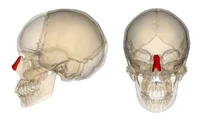

| Partie orange | Incus | 16%

| Partie marron | Stapes | 14%

| Partie beige | Malleus | 7%